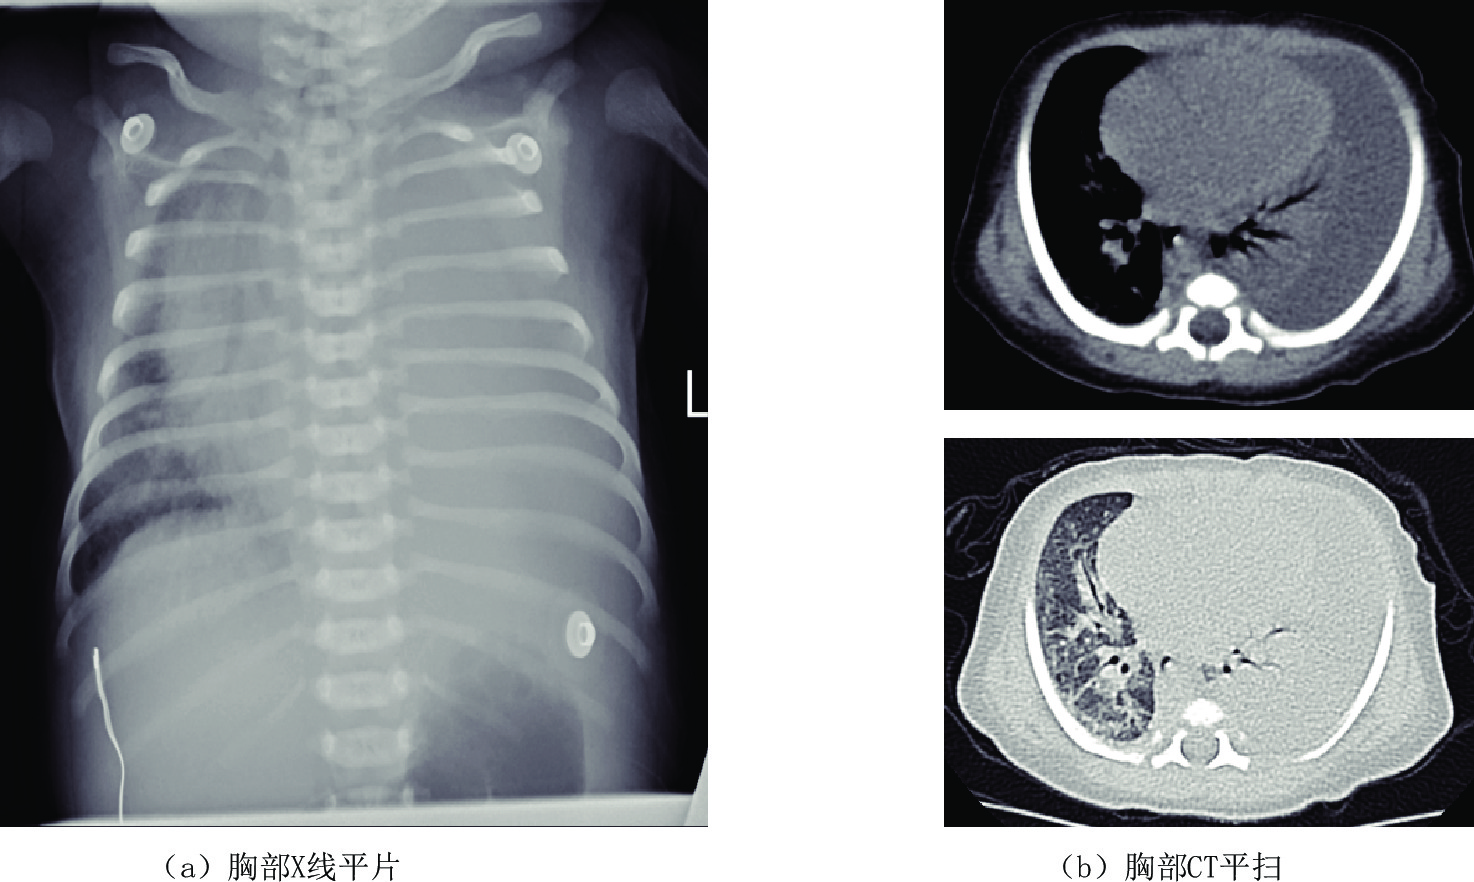

近年来,由于新生儿胸腔手术和中心静脉置管损伤胸导管或大淋巴管导致淋巴液或乳糜液的漏出。对于新生儿乳糜胸影像学检查方法首选胸部X线平片,表现为一侧或双胸腔致密,心缘消失,一侧胸腔积液时,心影纵隔向健侧移位,肋间隙增宽,胸部CT平扫为中-大量胸腔积液,相邻肺脏受压,胸腔穿刺引流,胸腔积液中甘油三酯>1.1 mmol/L,或白细胞计数>1×109/L,且以淋巴细胞为主,即可诊断新生儿乳糜胸(图1)。

原发性肺淋巴管扩张症为先天性肺间质发育异常,一般在胚胎发育的第15周左右发生,临床表现为新生儿出生后不久出现进行性呼吸困难、发绀,吸氧后不能缓解导致呼吸衰竭,预后差,极少数可存活,但存活的患儿一般有慢性咳嗽、喘息等症状。

X线胸部平片表现为弥漫的肺间质病变和或囊性变,高分辨CT扫描为最佳检查方法,表现为弥漫性或节段性的一侧或双侧肺小叶间隔增厚,伴磨玻璃影,可有少量的胸腔积液,纵隔增宽不显著及肺门增大不明显,弥漫性受累多见于新生儿及婴幼儿(图4)。

图 1 男,6天。以"生后气促6天"入院。左侧大量胸腔积液,胸水常规检查提示白细胞升高,胸水内甘油三酯含量高—新生儿乳糜胸

Figure 1. Male, 6 days old, admitted to hospital with "postnatal shortness of breath for 6 days". Large amount of pleural effusion of the left side. Routine examination of the pleural effusion indicates elevated leukocytes and high triglyceride content in pleural effusion-neonatal chylothorax